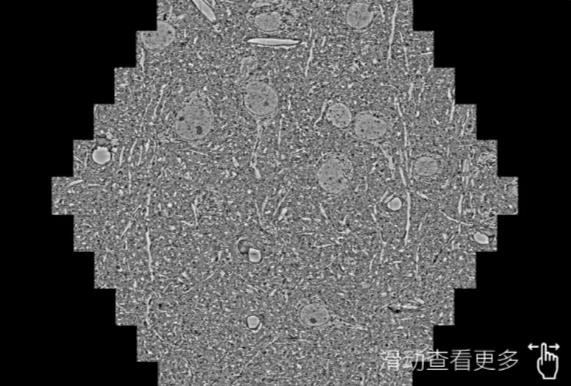

鼠脑切片。左图使用滨海蔡司滨海扫描电镜MultiSEM706对165μmx143pm面积区域成像,耗时仅需1.5秒。右图为鼠脑切片中30μm区域放大效果。样品由芝加哥大学B.Kasthuri提供。

使用蔡司高速滨海扫描电镜MultiSEM对1mm²人脑皮层组织进行高分辨成像,并对其中的各种细胞结构进行三维重构分析。左图展示了2x3mm²组织平面中锥体神经元的三维重构效果。右图显示了局部体积神经元三维重构。图像由哈佛大学chtman实验室提供,渲染图由D. Berger 制作。